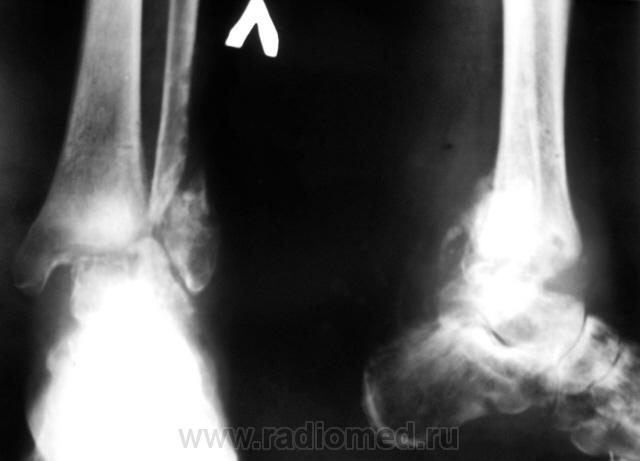

Пожилая женщина была доставлена из дома. После падения на улице, лечилась подручными средствами. считая, что пройдёт всё само собой. Но видно не получилось.

Похоже, что это дела давно минувших дней. Несросшийся перелом н/л с подвывихом стопы к наружи, разрывом ДМС. Состояние после МОС пластиной. Консолидированный перелом пяточной кости. Вполне вероятно, что свежего здесь ничего нет.

подвывих стопы не только кнаружи, но и кзади, вероятнее всего + к нар лодыжки и разрыву ДМС был сломан и задний край, на стопе она ходит давненько, с полной нагрузкой, древняя травма

Вполне возможно, трудно разглядеть на боковом снимке.

вначале показалось, что здесь сформировался ложный сустав. Да ещё картина немного напоминает остеомиелит.